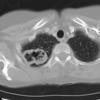

Case 14 RLL pneum CT

Date: 04/17/2005

Views: 5643